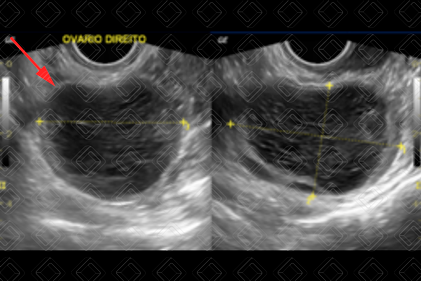

Descrição das figuras 5 e 6: Paciente de 46 anos, feminina. Ultrassonografia da pelve, estudo transvaginal, evidenciando ovário direito com dimensões muito aumentadas, as custas de formação heterogênea, predominantemente hipoecoica, contendo septos e debris no seu interior (seta vermelha). Foi orientada acompanhamento em 2-3 meses, com novo ultrassom e a lesão regrediu, sugerindo a possibilidade de cisto hemorrágico (vale ressaltar que a diferenciação entre cisto hemorrágico e endometrioma muitas vezes pode ser bem difícil no estudo de imagem).

Cisto hemorrágico ovariano (figuras 5 e 6): Na ultrassonografia, se apresenta como lesão heterogênea, predominantemente cística, contendo septos e/ou debris no seu interior. O acompanhamento é necessário e recomendado nas pacientes em idade fértil com lesões acima de 5 cm (controle em 6-12 meses: a lesão tem que regredir). Pacientes na pós-menopausa com lesões acima de 5 cm: complementar com ressonância magnética e/ou cirurgia.